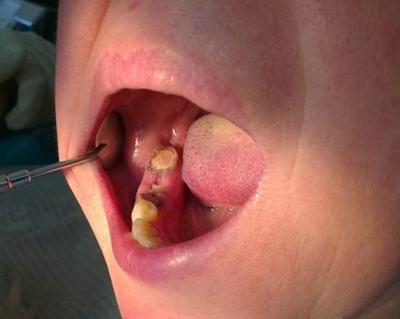

Кюретаж лунки зуба при альвеолите

- Под анестезией удаляется нагноившийся кровяной сгусток, пищевые остатки, некротический налет со стенок лунки. Без удаления некротического налета и распада кровяного сгустка (содержащих огромное количество инфекции) – любое лечение будет бесполезным.

- Лунка промывается антисептиками, просушивается, после чего она заполняется антисептическим средством (йодоформной турундой). Обычно каждые 4-5 дней турунду необходимо менять, т.е. вам придется сходить к врачу не меньше 3 раз.

Как проводится эта методика – если лунка пустая, то под анестезией костные стенки лунки выскабливаются кюретажной ложкой, чтобы создать кровотечение и лунка заполнилась кровью (видео 3). Если же лунка заполнена грануляциями, то их тщательно выскабливают, т.е. делают тот же кюретаж (видео 4). Далее в обоих случаях после того как лунка заполняется кровью – в глубь лунки кладется противовоспалительное лекарство (Альвожель), а на слизистую накладывается несколько швов, чтобы сблизить края раны. Сразу же назначаются антибиотики.